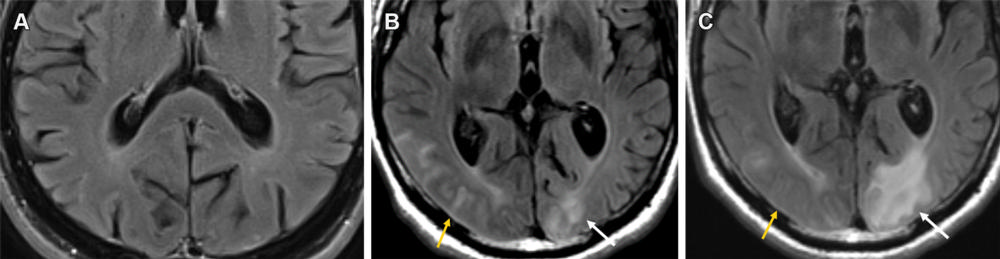

Figure 9. Mild ARIA-E (edema and effusion) in a 61-year-old man receiving aducanumab therapy. (A, B) Baseline pretreatment axial MR image (A) is unremarkable, with development of effusion (B) in the right occipital lobe (yellow arrow) and edema in the left occipital lobe (white arrow) on an axial MR image obtained 3 weeks after the target dose infusion (10 mg/kg). (C) Follow-up MR image after the fourth round of infusion shows near-complete resolution of the right occipital effusion (yellow arrow) with worsening of the left occipital lobe edema (white arrow). This was graded as mild throughout and therapy was continued, with complete resolution of all imaging changes at the seventh-week MRI examination.

High-res (TIF) version